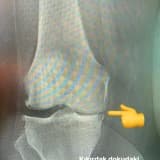

Ön çapraz bağ yaralanması şüphesinde fiziksel muayene sonrası direk grafi ve MRG yöntemi kullanılır. Direk grafide çapraz bağların kemiğe yapışma yerlerinde kopma kırıkları görülebilir. Ama bağ yaralanmalarında en güvenilir tanı yöntemi MRG’dir.